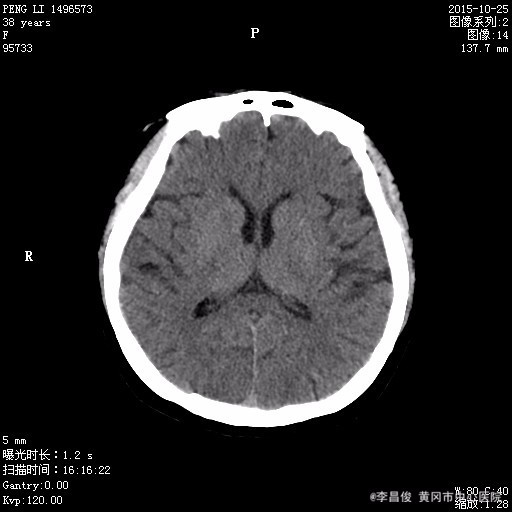

患者,女,38岁,2015年10月25日中午十二时赴酒宴时突发意识障碍,四肢抽搐,口唇发绀,双眼向上凝视,持续约十分钟后人意识逐渐清楚,伴恶心呕吐数次,遂急送我院120,行头部CT:脑萎缩,建议结合临床必要时行MRI检查,并以"癫痫"收住我科。 起病来,患者精神食欲睡眠差,大小便正常,体力下降,体重未有明显改变。 既往胃溃疡病史,有多次摔伤史,每天饮啤酒4-5瓶,饮白酒一斤;饮酒20年,每天吸烟20支,20年。

体格检查:BP130/90mmHg、 HR90次/分、 R16次/分, T36.5℃ 神清,精神欠佳,步入病房,查体合作。全身皮肤巩膜无明显黄染,结膜充血,全身多处淤青。颈软,甲状腺未及,双肺呼吸音清,未闻及明显干湿啰音,心律齐,各瓣膜区未闻及明显病理性杂音,腹软,肝脾肋下未及,双下肢不肿。 专科情况:神清,双侧瞳孔等大等圆,对光反射灵敏,四肢肌力肌张力正常,双侧病理征阴性,四肢有震颤。 辅助检查结果: 2015.10.25 头部CT:脑萎缩,建议结合临床必要时行MRI检查。2015.10.27 头部MRI:1.脑白质疏松;2.小脑萎缩;3.筛窦炎。 2015.10.26 血常规:白细胞 9.08*10^9/L,红细胞 3.47*10^12/L,血红蛋白 132g/L,血小板 88*10^9/L,中性粒细胞比率 92.2%;肝肾功能血糖血脂电解质:谷丙转氨酶 65.1U/L,谷草转氨酶 139.4U/L,尿酸 644.2umol/L,葡萄糖 8.16mmol/L,总胆固醇 9.93mmol/L,高密度脂蛋白胆固醇 3.87mmol/L,低密度脂蛋白胆固醇 4.86mmol/L,同型半胱氨酸 58.21umol/l;肌肉酶谱:磷酸肌酸激酶 309.1U/L,乳酸脱氢酶 397U/L;